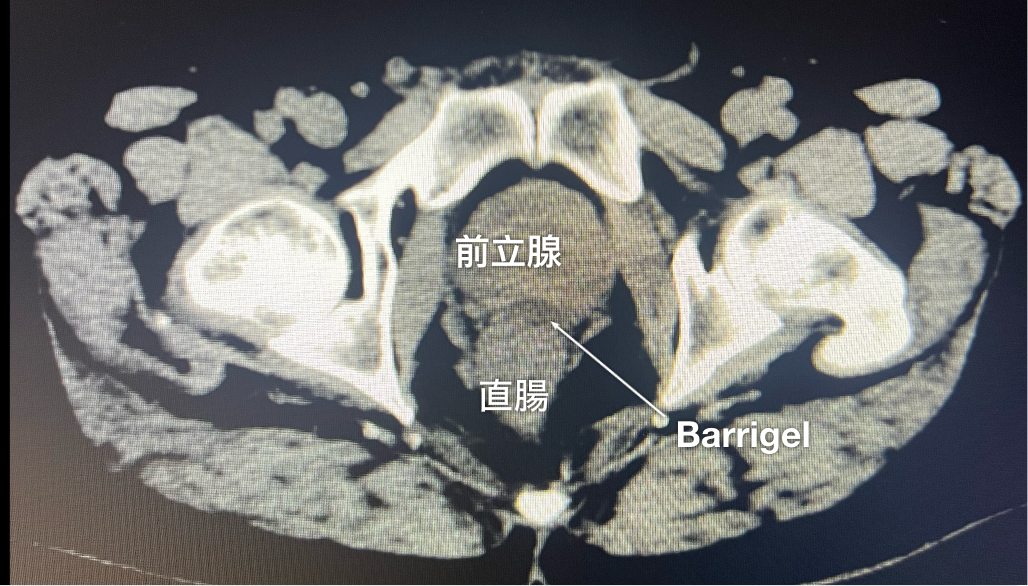

CT画像

CT画像提供:Gregory Bell, MD

Interventional Radiologist; Texas, United States